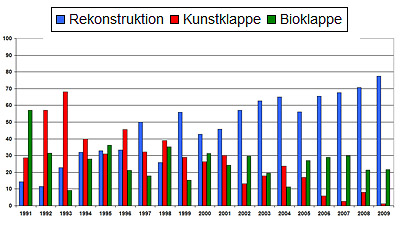

البته باید گفت با طولانی تر شدن و بهتر شدن دریچه های بیولوژیکی روند جهانی به سمت استفاده بیشتر از دریچه های بیولوژیکی است.